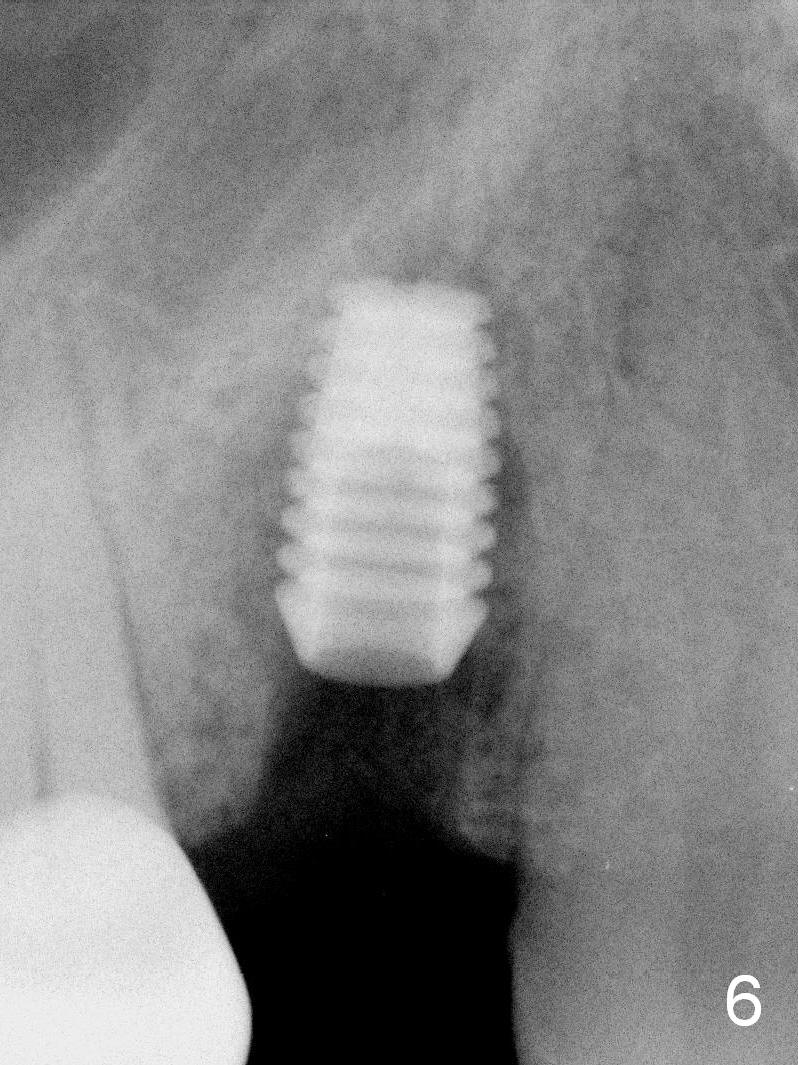

A 68-year-old man has pain and swelling associated with the tooth #5 (Fig.1). The fistula (*) is connected to the periapical radiolucency using a gutta percha (Fig.2 <). There are deep pockets distobuccal and lingual. The lingual root is found to have oblique fracture upon extraction. The distobuccal plate perforates (Fig.3). Collagen plug is placed. The buccal plate is concave (Fig.4) and socket density is low 2.5 months post extraction. Three months post extraction a 4.5x8 mm Bicon implant is placed after reamer and osteotome osteotomy (Fig.6). Bone density around the implant appears to increase 5 months post placement (Fig.7). Porcelain-fused-to-metal crown is cemented 2 weeks later. Bucco-occlusal porcelain chips 2 months post cementation. The patient decides to redo the crown. PA is taken before crown removal (Fig.8: 3 year 10 months post cementation). When a straight abutment is removed (Fig.9 A), a 15° angled abutment has to be used (Fig.10 red) for restoration.